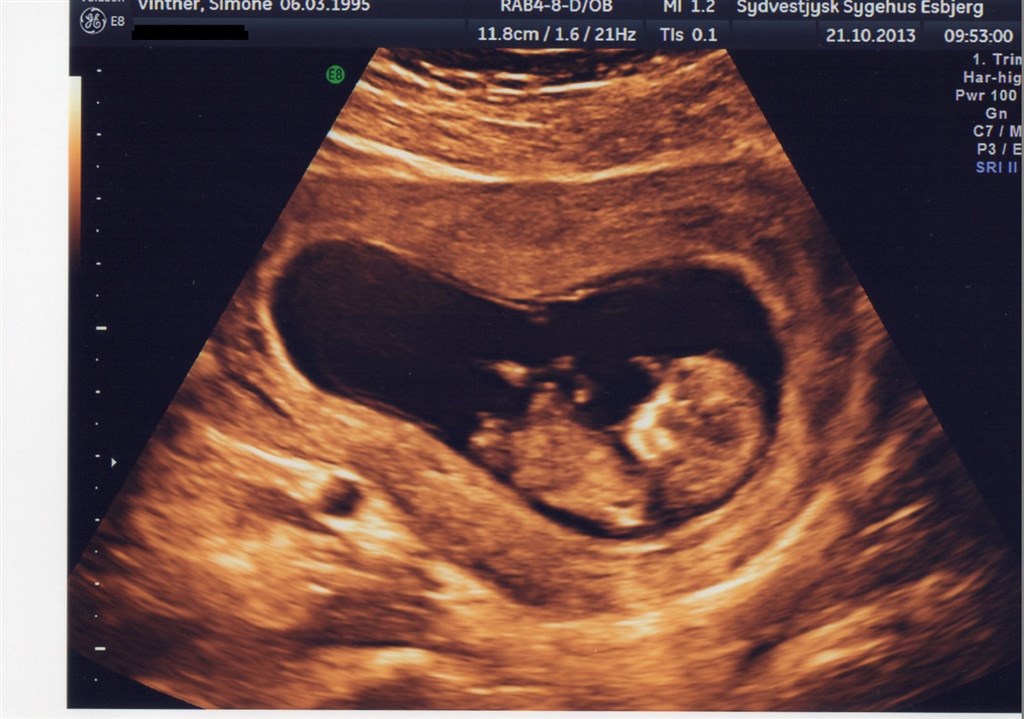

Ja, jeg må hoppe fra April-gruppen hvor jeg havde termin 30/4 og herover, efter det blev vist til NF at jeg har termin 7/5.

Vil lige vise et lille billede af frikadellen, fra NF.